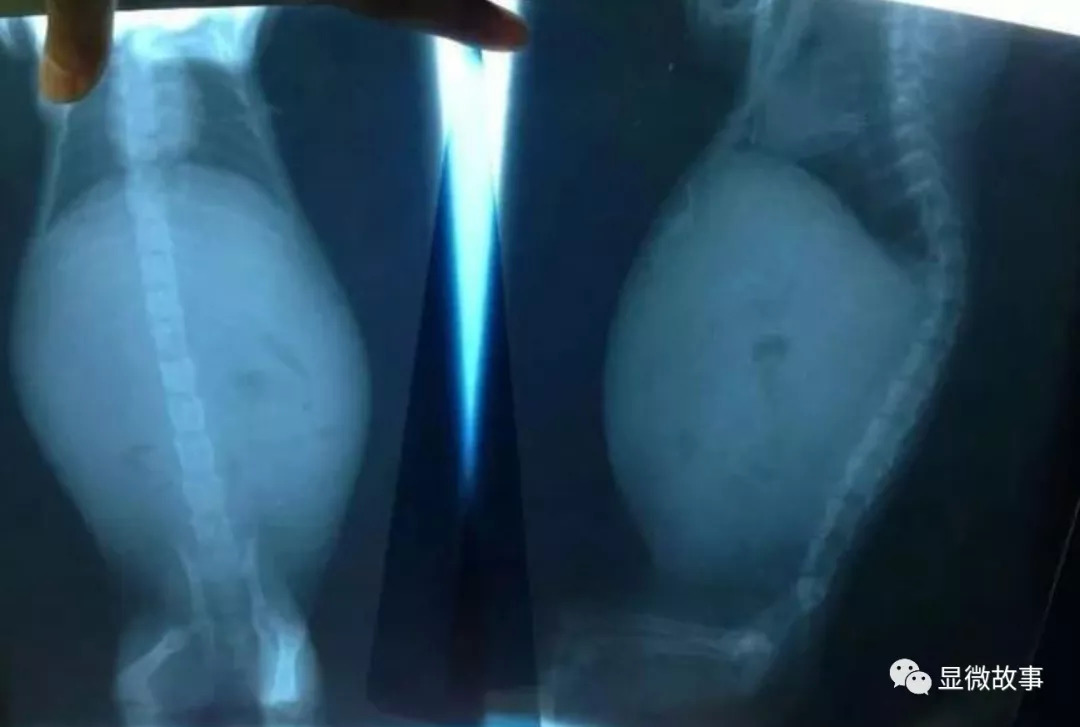

养猫的人应该都听说过猫传腹,全称猫传染性腹膜炎,这种病致死率高达95%。

但爱猫心切的主人肯定不能放弃这两款被证明初步有效的药,毕竟猫传腹基本等同于猫中绝症,用药不一定好,但不用药,猫一定会因为腹水导致的其他脏器衰竭致死。

这对猫来说也挺折磨的,腹水会压迫肺部,最后呼吸衰竭。